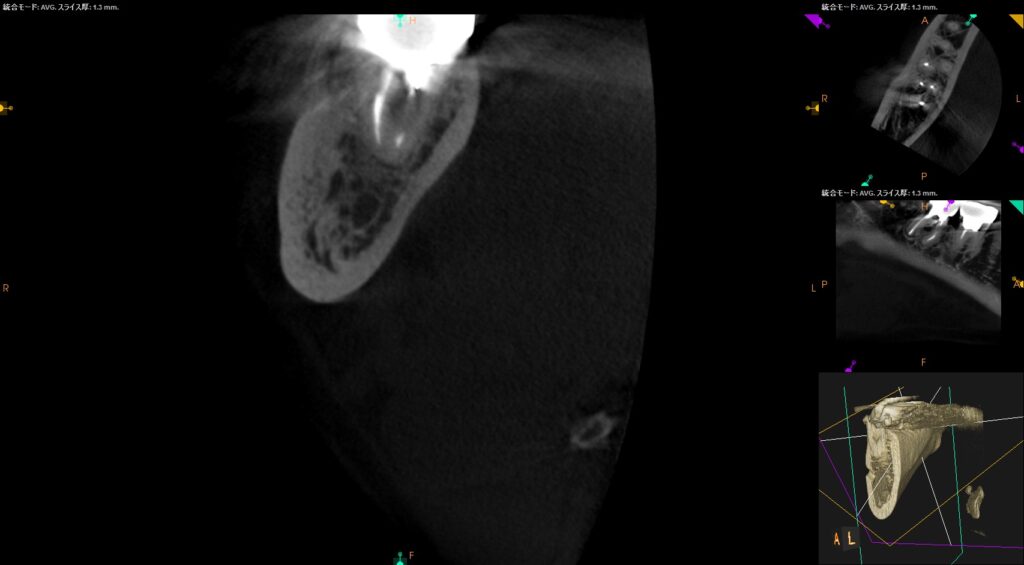

CT写真

11年後、当時の主訴であった右下一番奥(7番)の根っこの先の黒くなっている部分は白く改善されているように見える。勿論、患者さんも不都合は訴えていない。しかし、顎骨内部の骨(海綿骨)の状態は一般的な歯科のレントゲンであるパノラマ、デンタルでは把握できないので、正確な情報を知りたい場合、歯科用CTによる精査が必要と言える。